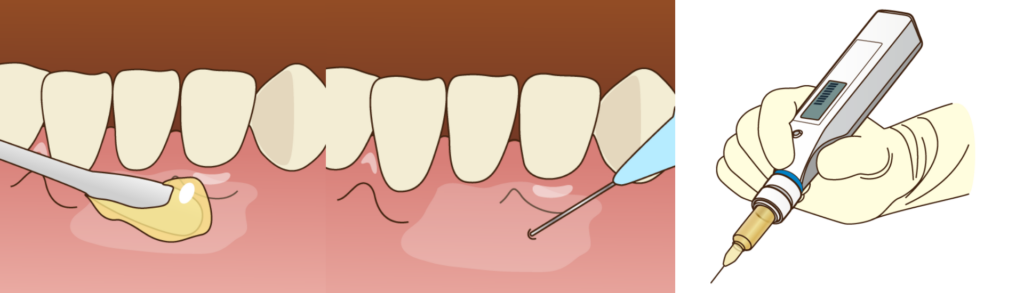

当院ではまず歯茎の表面にジェル状の「表面麻酔」を塗布します。感覚が鈍くなったところで針を入れますので、針が刺さる痛みはほとんど感じません。さらに、麻酔液の注入には「電動麻酔注射器」を使用します。

人の手で注射を行うと、どうしても注入スピードにムラができ、その圧力の変化が痛みとなって伝わります。

電動麻酔器はコンピュータ制御により、一定の非常にゆっくりとした速度で麻酔液を注入することが可能です。これにより、組織への圧力を最小限に抑え、無痛に近い状態での麻酔を実現しています。

特に、詰め物をする前の清掃や防湿(唾液が入らないようにすること)といった、地味ですが治療の予後を左右する基本工程を徹底的に行います。また、治療と並行して行うクリーニングや歯石除去においても同様です。